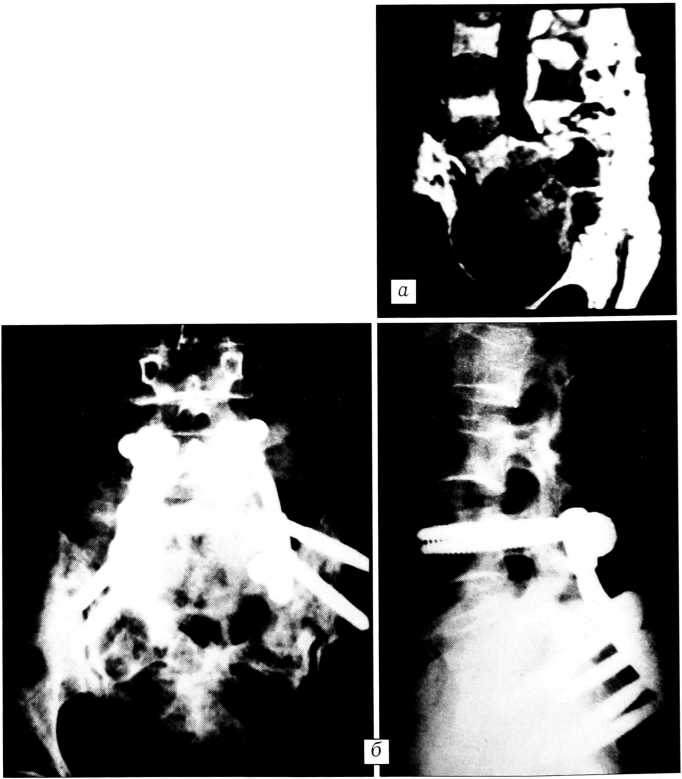

Рис. 3. Больная С. 51 года. Диагноз: нейрогенная опухоль крестца. На МРТ (а) деструкция крестца с наличием экстравертебрального компонента и сдавлением дурального мешка. Оперирована в два этапа: 1) субтотальное удаление опухоли, спондилодез фиксатором «Медбиотех»; 2) удаление всей опухоли реберно-паховым доступом (б). Гистологическое исследование: нейрофиброма.

В последние годы в Республиканском центре спинальной патологии и патологии позвоночника на базе БелНИИТО разрабатываются новые подходы к лечению больных с опухолями позвоночника (И.Р. Воронович, А.М. Петренко, А.В. Бабкин, С.В. Макаревич и др.), когда оперативное вмешательство завершается стабильным металлоостеосинтезом. В верхнешейном отделе используется наружная стабилизация гало-аппаратом. Созданный совместно с фирмой «Медбиотех» аппарат имеет специальные шарнирные соединения и форму штанг, позволяющие проводить интубацию трахеи и выполнять операцию из переднего или заднего доступа, не снимая аппарат. Погружной остеосинтез разработанными в институте титановыми транспедикулярными стержневыми фиксаторами не мешает проведению лучевой и химиотерапии. Совместно с фирмой «Медбиотех» разработан и внедрен в практику универсальный фиксатор для грудного, грудопоясничного и поясничного отделов позвоночника.

Первым этапом осуществляется стабилизация из заднего доступа металлоконструкцией, тип которой выбирается с учетом конкретной ситуации. Если имеется поражение дорсальных отделов позвоночника со сдавлением спинного мозга, то параллельно производится удаление опухоли до корней дуг с декомпрессией дурального мешка. По нашему мнению, при первичных злокачественных, метастатических и литических доброкачественных опухолях целесообразно осуществлять стабилизацию грудного отдела позвоночника интраламинарным контрактором, грудопоясничного — комбинированным, поясничного — транспедикулярным фиксатором. Вторым этапом выполняется тотальное удаление опухоли и тела позвонка из переднего или переднебокового доступа. Такая тактика позволяет рано начинать реабилитацию больных и вертикализировать их без гипсовых корсетов.